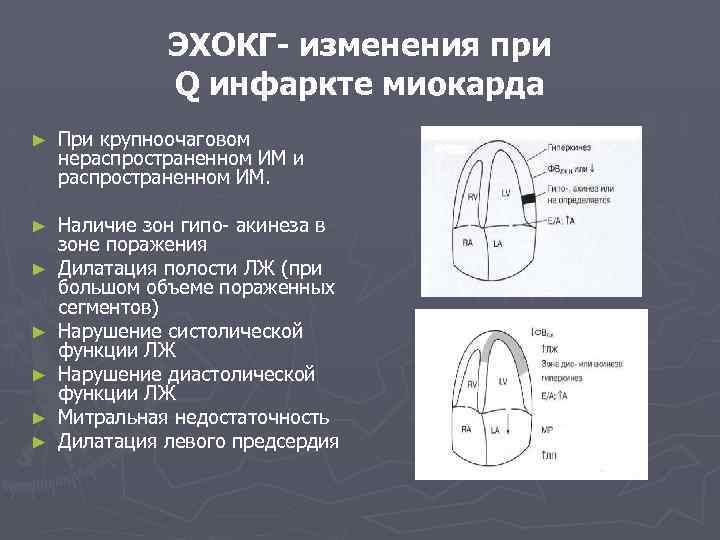

ЭХОКГ- изменения при Q инфаркте миокарда ► При крупноочаговом нераспространенном ИМ и распространенном ИМ. ► Наличие зон гипо- акинеза в зоне поражения Дилатация полости ЛЖ (при большом объеме пораженных сегментов) Нарушение систолической функции ЛЖ Нарушение диастолической функции ЛЖ Митральная недостаточность Дилатация левого предсердия ► ► ►